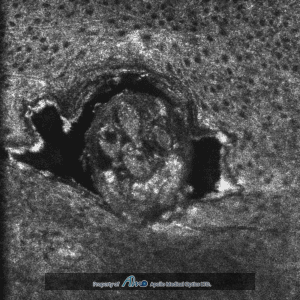

In vivo characterization of extramammary Paget’s disease by ultra‐high cellular resolution optical coherence tomography

Authors: Wang, J., Wang, Y., & Wu, Y

From Journal: Skin Research and Technology. 27(1):114-117

08/06/2020